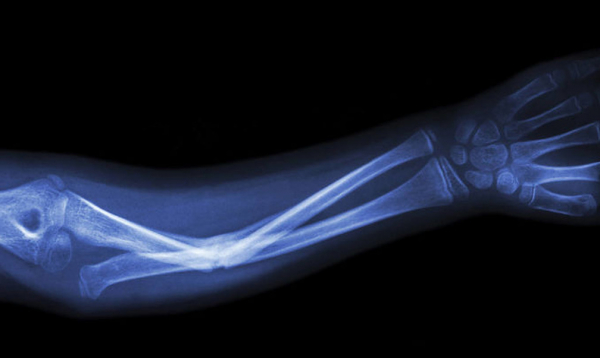

К биоматериалам, из которых изготавливаются имплантаты, используемые для протезирования, предъявляются особые требования. Во-первых, они не должны оказывать отрицательного воздействия на живые ткани, находящиеся в непосредственном контакте с ними внутри организма. Во-вторых, у искусственной кости должна была пористая структура. Только тогда клетки костной ткани и кровеносные сосуды прорастают внутрь имплантата. В-третьих, необходимо, чтобы материал обладал биологически активными свойствами, мог влиять на физиологические процессы в организме: стимулировать рост, способствовать миграции, делению и дифференцировке клеток.

По отдельности оба ингредиента, взятые учеными для создания нового материала, уже используются в разных сферах хирургии. Порошки синтетического силиката кальция применяют для устранения мелких челюстно-лицевых дефектов, при наращивании костной ткани и зубном протезировании. Керамика, способная выдерживать значительные нагрузки, применяется в более масштабных операциях, например, при замене целой кости или сустава.

Преимущество созданного синтетического материала, представляющего наноструктурированный силикат кальция (волластонит), в том, что он биологически активный и положительно влияет на метаболизм при введении в организм, и при этом обладает необходимой для имплантатов структурой и прочностью. А добавки наночастиц благородных металлов — золота и серебра — придают имплантатам антибактериальные и противовоспалительные свойства.

Полученные из новых материалов протезы ученые протестировали на мышах, и отметили их исключительно высокую биологическую совместимость. Их можно будет использовать для протезирования пациентов любого возраста. Ученые надеются, что их открытие в ближайшем будущем позволит наладить производство относительно дешевых отечественных биоматериалов для костной хирургии.